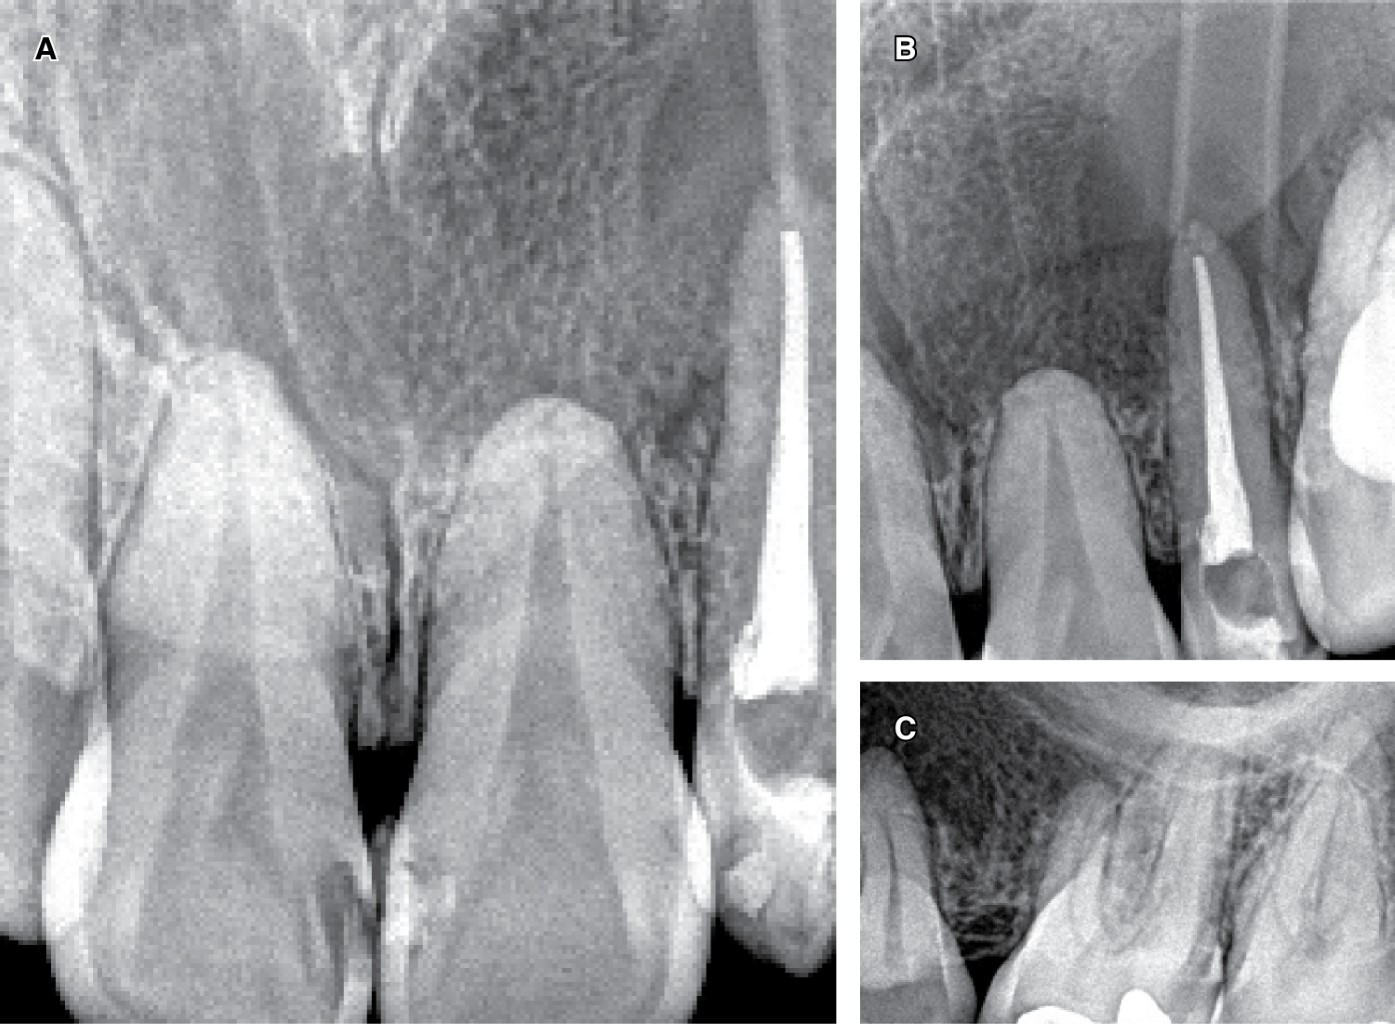

An orthopantomography and a computed axial tomography showed a large lytic lesion in almost the entire left upper hemimaxilla without compromising the nasal cavity and maxillary sinus, whose anterior limit was in the corresponding central incisor sector and its posterior limit was delimited by the left first molar.

Figure 2 illustrates the different tomographic sections that allow observing the osteolytic image compatible with the cystic process. All the teeth involved showed an absence of signs of pathological rhizolysis and preserved pulp vitality, except for the left upper lateral incisor associated with DI. The clinical diagnosis was a maxillary inflammatory cyst associated with pulp necrosis of the upper lateral incisor.

• 3) Monitoring and control: monthly clinical and radiographic control was carried out. The patient continued with the washing on an outpatient basis for six months. Bone trabeculae formation and a notable lesion reduction (evident in the intraoral X-ray control) were observed near to the anteroposterior limits of the cystic lesion in the three and 6-month control (Figure 4).